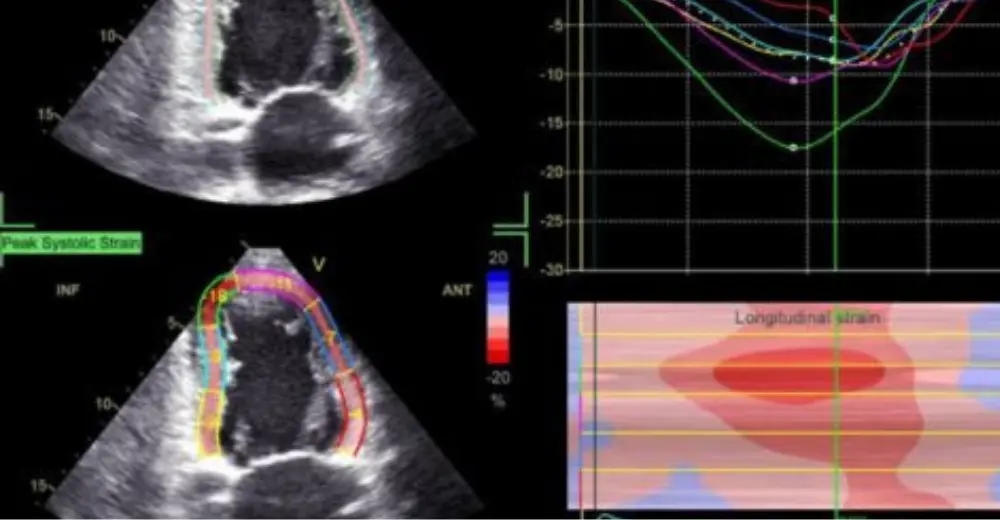

Це сучасна методика ехокардіографії (ЕхоКГ), заснована на аналізі руху спеклів (акустичних точок або плям), отриманих в 2D (двовимірному) режимі. Найчастіше оцінюється деформація (стрейн) міокарда у трьох площинах: повздовжній (longitudinal), радіальній (radial) та циркулярній (circumflex).

Найчастіше оцінюється глобальний повздовжній стрейн (GLS) лівого шлуночка. Математично оброблений результат подається у вигляді 16- або 17-сегментної діаграми (bull`s eye), графіків та значень GLS, отриманих з трьох різних зрізів (LAX, A2Ch, A4 Ch) та середнє значення GLS